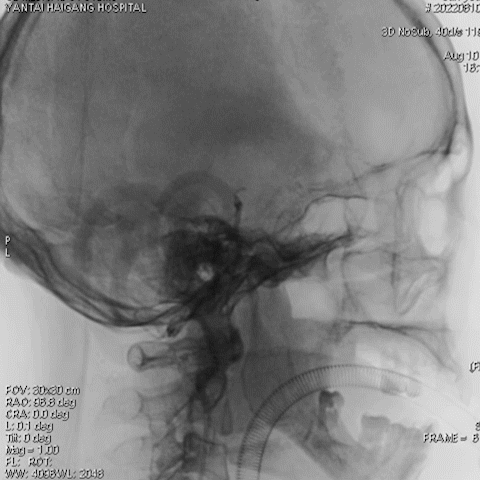

右椎动脉造影:

导丝怎么扩【载药时代 球扩天下】NOVA DES®颅内药物洗脱支架在椎动脉颅内段重度狭窄的应用二例_https://www.jmylbn.com_新闻资讯_第24张

导丝怎么扩【载药时代 球扩天下】NOVA DES®颅内药物洗脱支架在椎动脉颅内段重度狭窄的应用二例_https://www.jmylbn.com_新闻资讯_第25张

导丝怎么扩【载药时代 球扩天下】NOVA DES®颅内药物洗脱支架在椎动脉颅内段重度狭窄的应用二例_https://www.jmylbn.com_新闻资讯_第26张

右椎动脉动脉正侧位:

导丝怎么扩【载药时代 球扩天下】NOVA DES®颅内药物洗脱支架在椎动脉颅内段重度狭窄的应用二例_https://www.jmylbn.com_新闻资讯_第29张

诊断

主要诊断:

1.右侧椎动脉V4段重度狭窄(90%);

2.高血压病2级 高危;

3.小脑梗死。